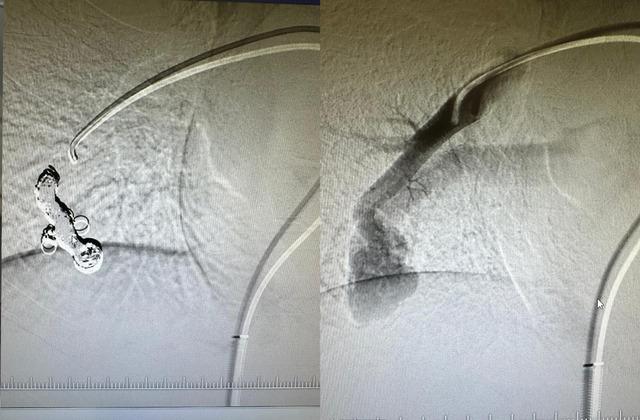

Doç. Dr. Hasan Gündoğdu ise tedaviyle ilgili bilgi verdi. Doç. Dr. Gündoğdu hastalıkla ilgili şunları söyledi: “Doğrusu böyle bir hastalığın hem tespit edilmesi hem de ilgili merkeze yönlendirilmesi çok zor bir iştir. Dr. Fazıl Can hocam hastalığı tespit edip ilgili merkeze yönlendirdi. Girişimsel radyoloji ekibi, hocam Dr. Mirsad ile birlikte hastamıza en hızlı şekilde müdahale etti.” Bizim için çok güzel bir operasyon oldu. Böyle bir operasyonu bölgemizde ve hastanemizde ilk defa başarıyla gerçekleştirdik. Oğlumuzun artık diğer çocuklarla aynı şekilde oynayabileceği ve tedavi edilmezse semptomlarının ortadan kalkacağı için mutluyuz. “Oksijen seviyesi düşük olduğundan çocuk oyun oynayamayacak ve hareket edemeyecek.” Bu hem çocukta psikolojik sorunlara yol açabilir hem de damar nodülü büyüyerek hastanın akciğerlerinde ciddi kanamalara neden olabilir” dedi.

Normalde kan, atardamarlardan ayrıldıktan sonra temizlenerek toplardamarlar yoluyla vücuda geri döner. Bunlar kılcal damar dediğimiz, filtre görevi gören damarlardan oluşur. Bizim hastamızda bu damar bağlantısında filtreleyici bir yapı yoktu. Bu durumda kan temizlenmeden doğrudan vücuda gidiyordu. Bu da oksijen seviyesinin düşük olmasına neden oldu. Testleri yaptık, teşhis koyduk. Ameliyatı girişimsel radyoloji ekibiyle birlikte gerçekleştirdik. Bu hastalarda en sık uygulanan müdahale yöntemi embolizasyon dediğimiz şantın kapatılmasıdır. Bu hastalar çok nadirdir. Genellikle yetişkinlikte teşhis edilir, ancak çocuklarda da bulabiliriz. Doğuştan olabilir. Biz hallederiz. Tedaviden sonra saturasyonu düzeldi. Hastalarımızdan gelen şikayetler de azaldı” dedi.